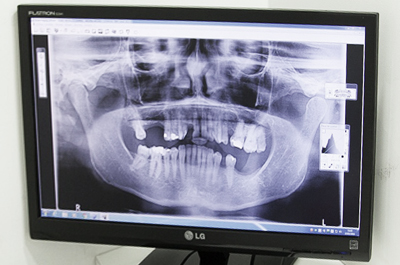

환자 상태 파악

치아, 뼈는 물론 당뇨, 고혈압 등

건강상태 전반 파악

• 2

수술 준비 및 진행

보철과 전문의와

구강외과 전문의의 협진

• 3

수술 장치 제작

컴퓨터 모의 수술을 토대로

수술 장치 디자인 및 제작

• 4

수술 진행

디자인 결과에 따라

정확한 수술 진행